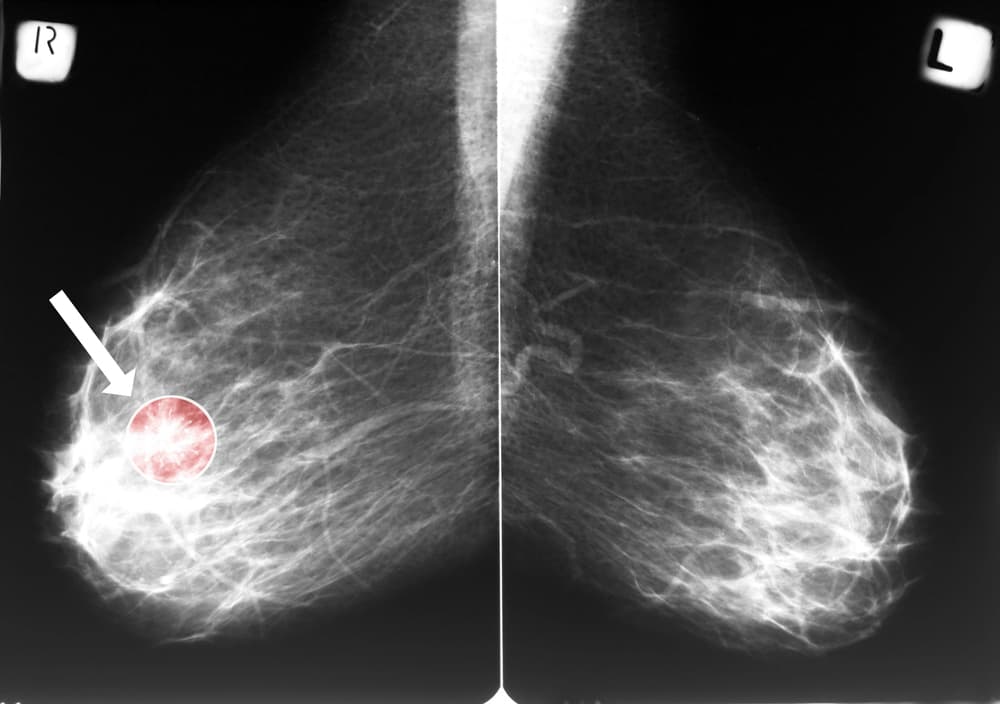

Podle odborných doporučení musí každý snímek z mamografu vyhodnotit dva lékaři. Některá centra přidávají navíc vyhodnocení AI. "Živí odborníci tak získali možnost porovnat svůj nález s doporučením strojového algoritmu, který se učil na milionech snímků," řekl Daneš.

Ukazuje se podle něj, že pokud AI označí nález za nízkorizikový, je tato pravděpodobnost kolem 99 procent. Šetří tak podle něj čas lékařům, kteří se mohou více věnovat náročnějším případům. U 20 procent snímků systém doporučí další posouzení člověkem. "Směřuje to k tomu, že v určitých oblastech medicíny to bude jednou lepší než ten doktor," dodal.